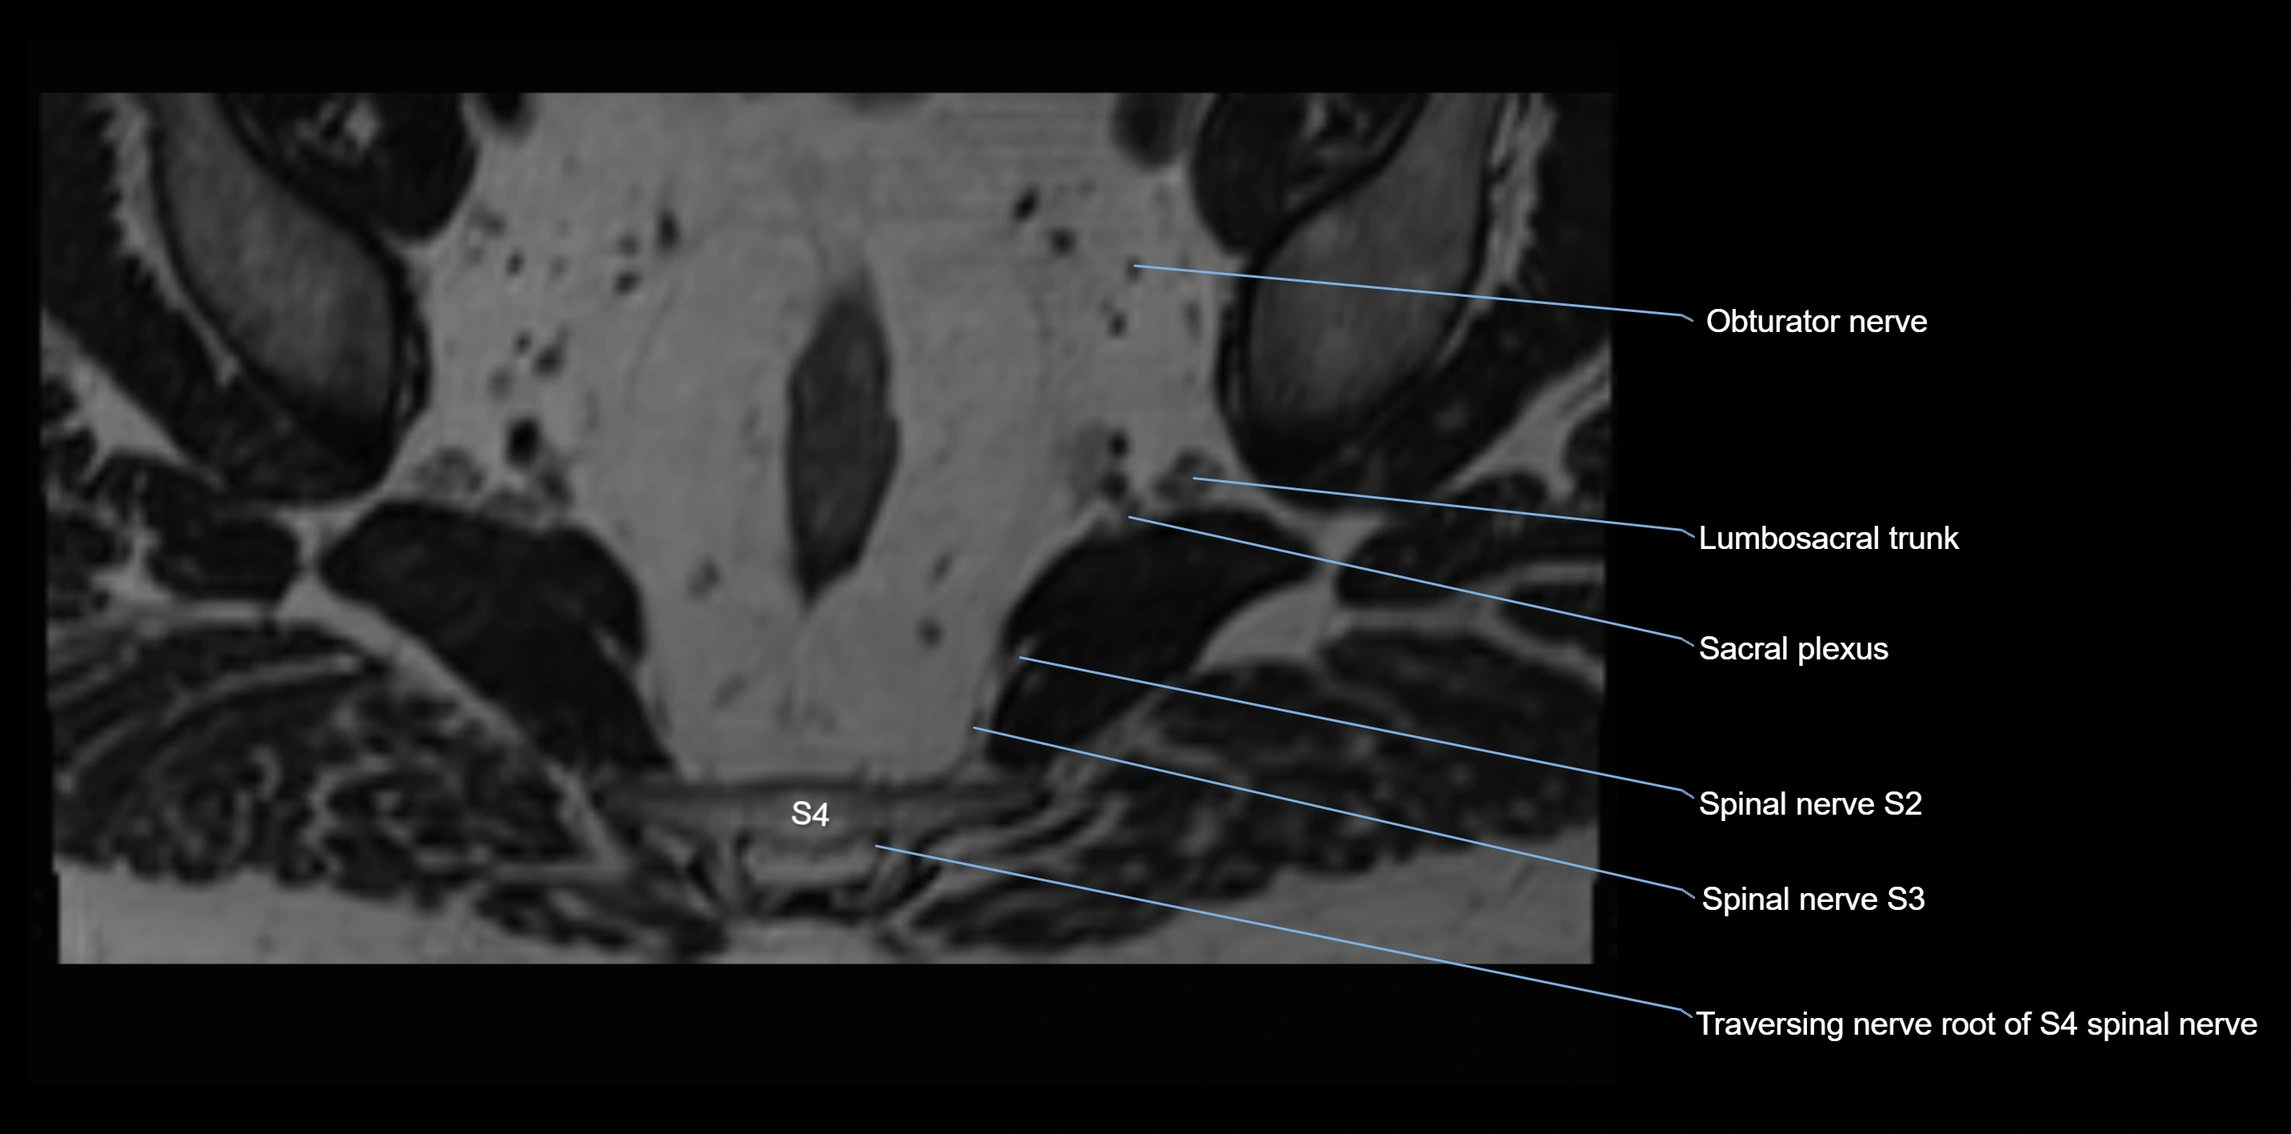

MRI image

image